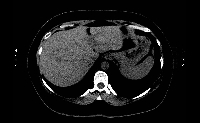

Πρόκειται για γυναίκα ασθενή 47 ετών, η οποία υποβλήθηκε σε κολονοσκόπηση για άτυπα γαστρεντερικά συμπτώματα. Διαπιστώθηκε αδενοκαρκίνωμα σιγμοειδούς με δύο σύγχρονες μεταστατικές εστίες στο δεξιό λοβό του ήπατος (εικόνα 1). Ακολούθησε σιγμοειδεκτομή. Έλαβε 12 κύκλους χημειοθεραπείας με Avastin και FOLFOX. Κατόπιν υποβλήθηκε σε δεξιά ηπατεκτομή (εικόνα 2). Στο παρασκεύασμα φαίνονται οι δύο μεταστατικές εστίες, η μεγαλύτερη εκ των οποίων είναι 4 εκατοστά (εικόνα 3). Ο όγκος του υπολοιπόμενου ήπατος ανήλθε από 39% σε 62%, ένα μήνα μετά την ηπατεκτομή (εικόνα 4). Δεν έλαβε μετεγχειρητική χημειοθεραπεία. Η ασθενής εξακολουθεί να είναι ελεύθερη νόσου.